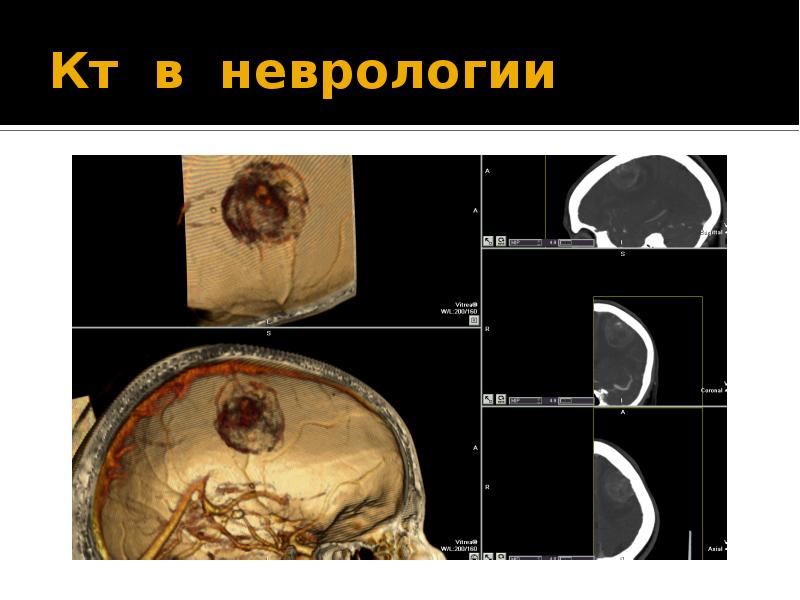

Компьютерная томография в неврологии презентация - 86 фото